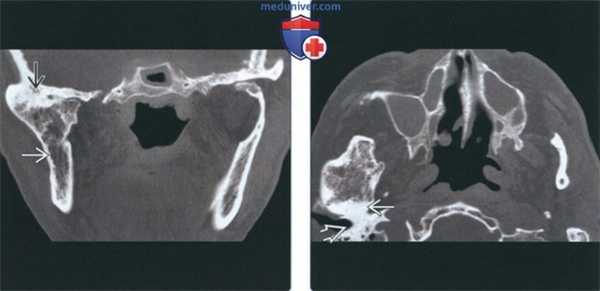

(Слева) На панорамной реформатированной КЛКТ у восьмилетней девочки с фиброзным анкилозом вследствие травмы и подмыщелкового перелома со смещением определяются крупные костные включения, сращенные с височной костью и нижней челюстью. Между включениями костной ткани определяется просветление, представляющее собой сохранившееся суставное пространство.

(Справа) На косой сагиттальной КЛКТ левого ВНЧС у взрослой женщины с фиброзным поствоспалительным анкилозом между мыщелком и суставной ямкой визуализируется суставное пространство в виде тонкого неравномерного просветления.